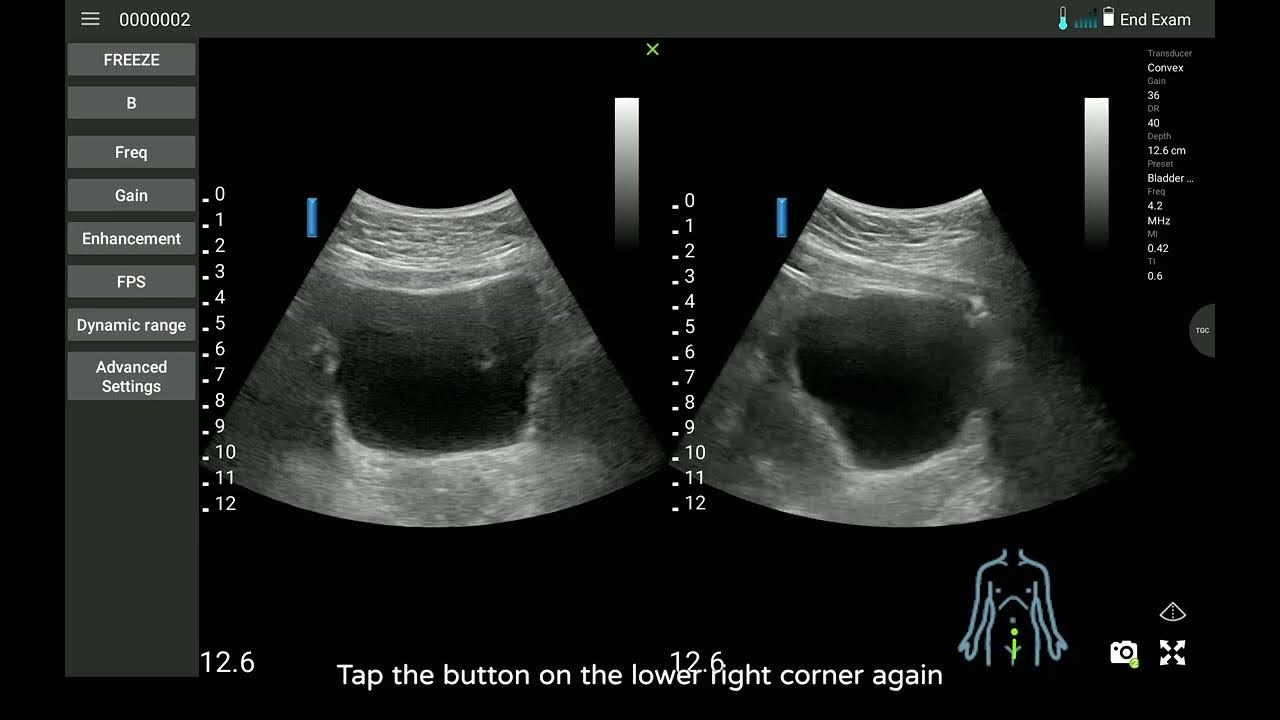

From www.youtube.com

313 Measuring the bladder volume 【Norland uREzpocus User Guide】 YouTube How Do You Measure Bladder Volume On Ultrasound It shows you how to assess the bladder properly using ultrasound in a step by step fashion. Estimates bladder volume based on ultrasound shape, length, width and height measurements. Bladder volume can be measured during an ultrasound (us) examination using the mathematical methods enumerated above. The volume of an ellipsoid is 4 ⁄ 3 π(a ⁄ 2)(b ⁄ 2)(c ⁄. How Do You Measure Bladder Volume On Ultrasound.